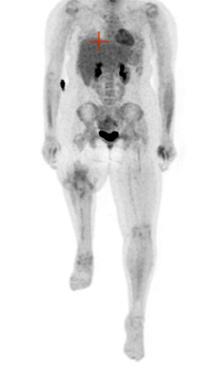

Sarcome d’Ewing

Le sarcome d’Ewing a été décrit la première fois en 1921 par James Ewing, cancérologue américain. C’est une tumeur osseuse à cellules rondes indifférenciées, plus précisément une tumeur neurœctodermique primitive. Il s’agit d’une tumeur extrêmement agressive, mais qui est très sensible à la radiothérapie. Il y aurait une translocation, c’est-à-dire une cassure ou une mutation dans les chromosomes 11 et 22. La maladie se localise principalement à la diaphyse de l’os long et parfois dans les vertèbres. La prédisposition serait 10 fois plus élevée chez les individus de race blanche plutôt que dans la population afro-américaine. Les données démographiques démontrent que ce sont les enfants qui sont les plus touchés ou les jeunes adolescents/adultes entre 5 et 20 ans, et il est extrêmement rare que ce cancer touche les gens au-delà de 20 ans. La prévalence est plus forte chez les garçons que chez les filles, et celles-ci ont de meilleurs taux de survie. Sur le plan radiographique, on décrit l’image du sarcome d’Ewing comme un « bulbe d’oignon », et la diaphyse est plutôt boursoufflée. Sur la scintigraphie osseuse (figure 1 ), la lésion apparaîtra plus

Antérieur

Postérieur